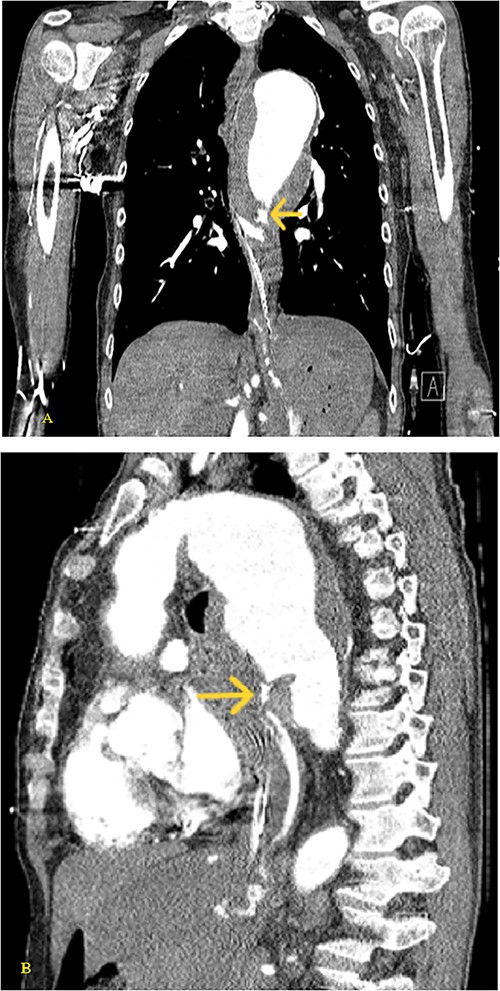

A 59-year-old male with no known previous medical history presented to a Level 1 trauma center after being discovered by EMS in a large volume of red blood. The event was unwitnessed by bystanders, so it was assumed that the mechanism was a traumatic fall with a resulting head bleed. During transportation patient lost pulses but returned to spontaneous circulation after cardiopulmonary resuscitation. The patient’s initial vital signs in the trauma bay were a blood pressure of 129/40 mmHg, a heart rate of 101 beats/min, and a Glasgow Coma Score of 3. The head was bandaged by EMS with red blood sticking to the patient’s hair, ears, and face. Upon unwrapping of the patient’s bandaged head, there was no source of bleeding nor was any trauma identified to the body. The patient was intubated and an orogastric tube was inserted with immediate drainage of 2L of bright red blood. The initial differential diagnosis was trauma in origin, including a basilar skull fracture with ingestion of blood or blunt abdominal trauma. Sonography identified no signs of internal peritoneal bleeding. Chest X-ray revealed large dilation of the thoracic aorta (Fig. 1). CT of the chest with IV contrast showed aneurysmal dilation of the ascending and descending thoracic aorta with max diameter of 65 mm, AEF at the level of pulmonary artery bifurcation and contrast extravasation into the esophagus and stomach (Figs 2–4). Octreotide was given and a massive transfusion protocol (MTP) was initiated with transfusion including 2 units of whole blood and 15 units of RBCs. Cardiothoracic surgery and interventional radiology were called to evaluate the patient; however, massive blood loss ultimately led to a myocardial infarction and the patient expired 75 min after admission.

(A) Coronal and (B) sagittal views of the arterial phase CT chest with IV contrast performed during the initial trauma evaluation show aneurysmal dilation of the thoracic aorta with contrast extravasation into the esophagus and stomach.